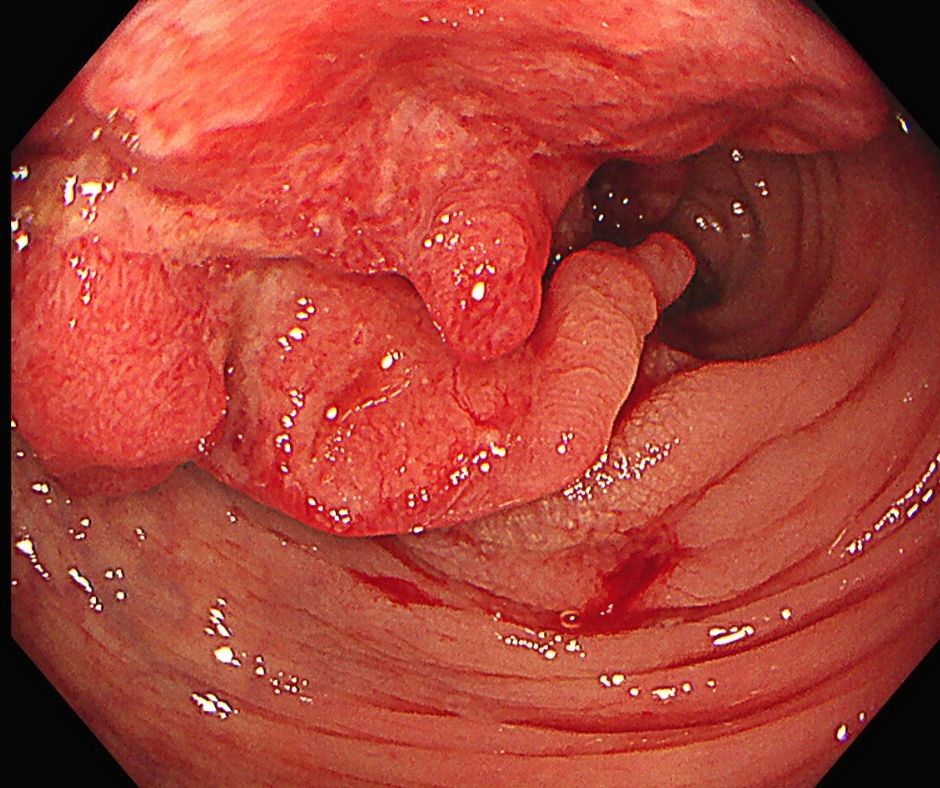

たなべ内科クリニックは、消化器を専門とする内科のクリニックで、患者さんの健康状態を、内視鏡や超音波検査、レントゲン、血液検査など各種検査により評価し診断・治療を行っています。